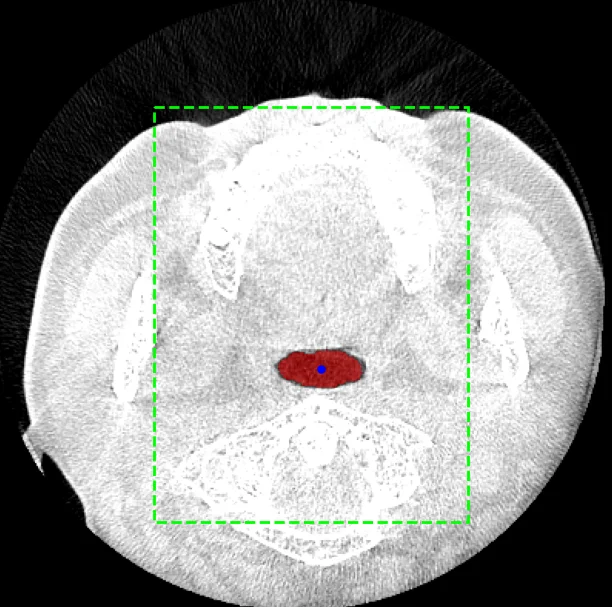

관심영역(연두색), Seed(파란색), 클러스터링 후 병합한 공기 영역(빨간색)

기도 내의 공기 영역을 Segmentation하는 Task의 가장 중요한 점은 영역 확장의 시작점이 되는 Seed를 정확하게 찍는 것입니다.

우선 850~3,000 의 HU 값으로 뼈를 찾고, 뼈의 바운딩 박스의 좌우 55% 범위, 전후 70% 범위로 Seed가 있을 만한 관심영역을 설정했습니다.

그리고 전체 볼륨의 하단 30% 슬라이스들로부터 Seed 후보군을 추출했습니다. 간혹 목뼈나 턱 밑 허공을 Seed 후보로 설정하는 경우가 있어서 관심영역에서 y축의 3/4 지점에 가까울수록 높은 score를 부여했습니다.